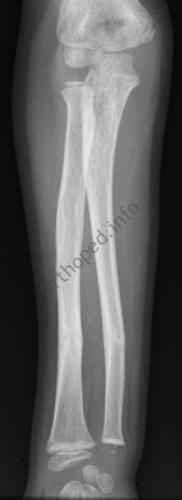

Fracture de l’avant-bras 31 mars 202519 mars 2024 par Damien Traitement Traitement orthopédique Embrochage centro-médullaire